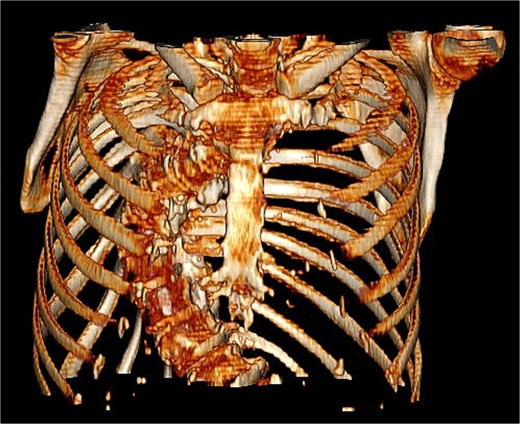

Preoperative imaging highlighted this significant spinal deformity and its impact on cardiac orientation and accessibility (Fig. 3). The scoliosis increased the complexity of the surgery, necessitating customized operative strategies. The patient underwent minimally invasive MVR and septal myectomy through a right mini thoracotomy. A mechanical valve was selected as a redo would be near impossible due to the cases uniqueness and inherent difficulty. Operative technique involved a 5 cm skin incision on the right upper breast at the 2nd ICS for a working port (Fig. 4), with additional ports in the 2nd and 4th ICS for camera and CO₂ venting. Extracorporeal circulation was established via femoral–femoral bypass through a groin incision to access the left femoral vessels for cannulation.